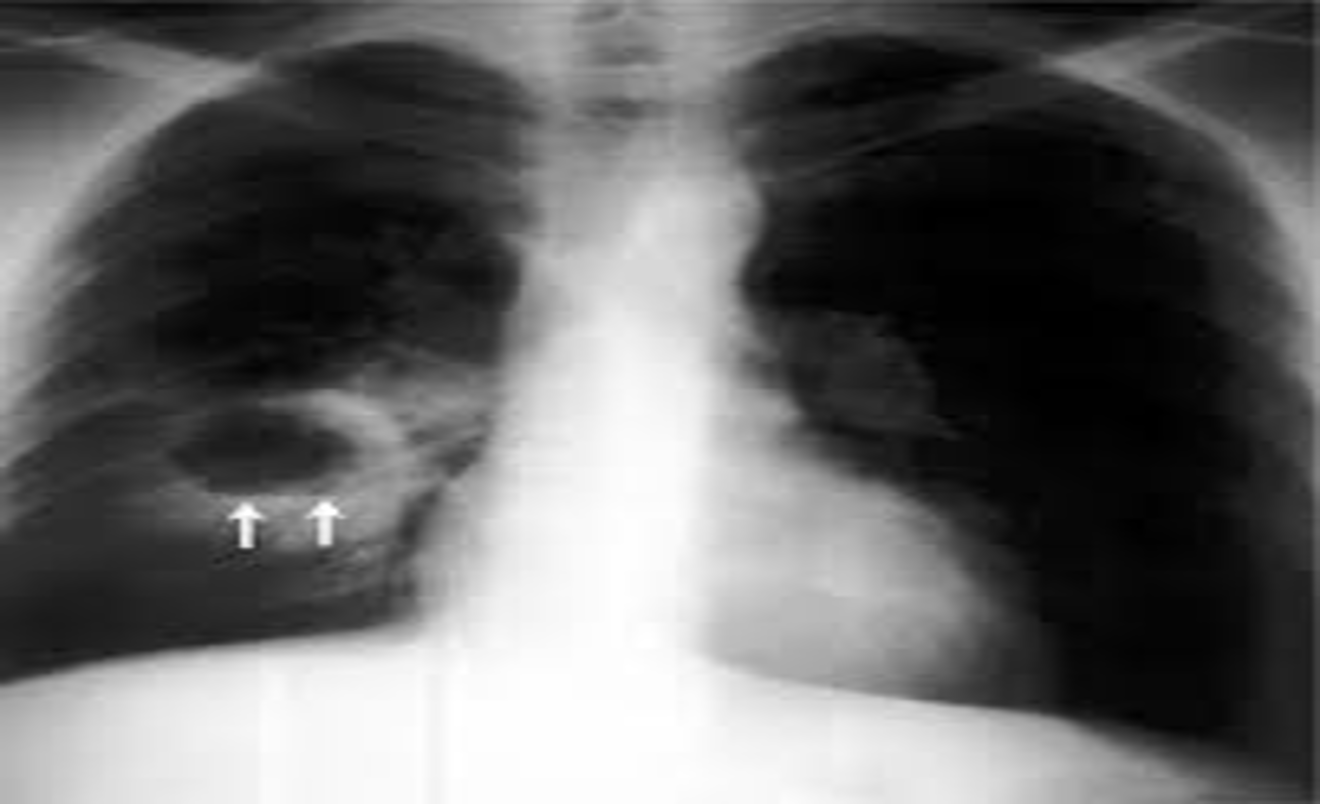

The diagnosis is suggested by a chest radiograph demonstrating a thick-walled cavity with an air-fluid level and confirmed by contrast-enhanced computed tomography .

Anterior view of a chest radiograph in a patient with thick-walled right lung abscess. The patient later developed a brain abscess.

Air fluid level

Cavitation (abscess formation):

The air is then seen as a transradiancy within the consolidation and an air–fluid level may be present